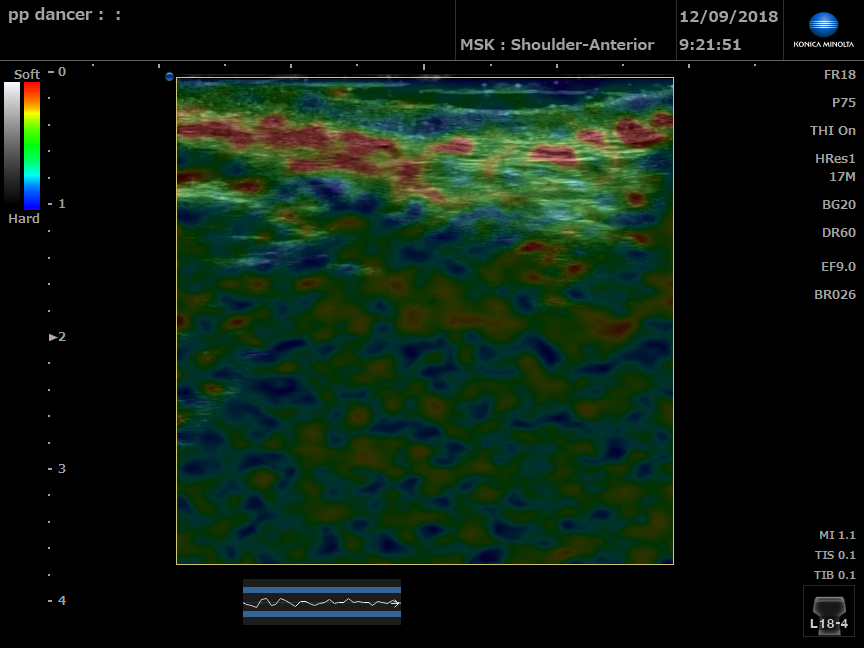

Strain Elastography of left perineal body

Strain Elastography of right perineal body